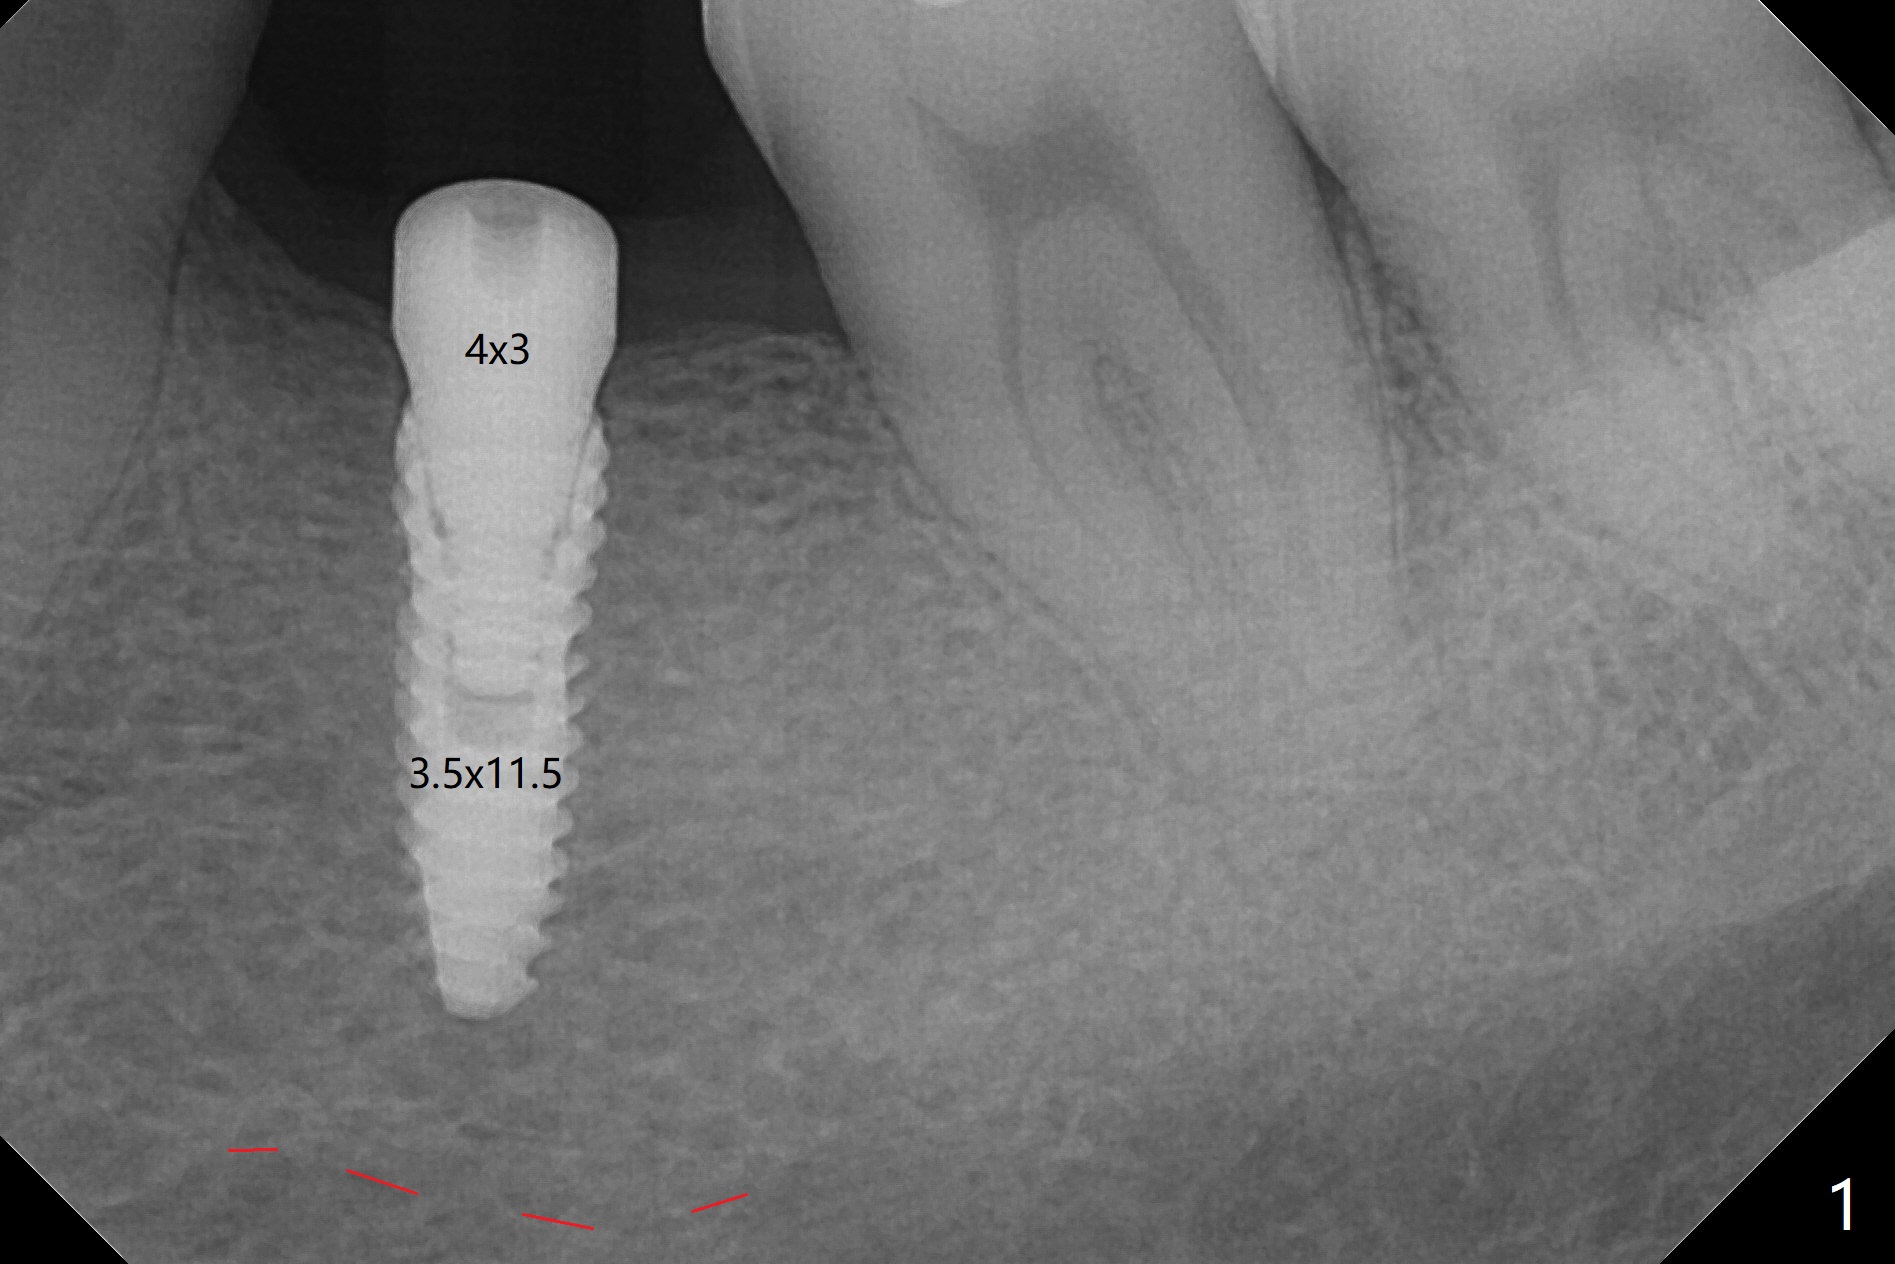

After placement of a 3.5x11.5 mm implant with ~ 50 Ncm at #19 (Fig.1,2), the narrow mesiodistal space seems difficult for uncover if a healing screw is placed. A 4x3 mm healing abutment is placed. To re-seat the existing RPD (Fig.3), the pontic (P) is reduced for clearance (Fig.4).